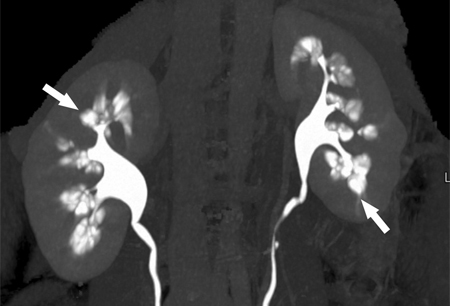

Medullary sponge kidney

Computed tomography (CT) urogram showing papillary blush with calculi within dilated collecting tubules (arrows)

From Maw AM, et al. Am J Kidney Dis. 2007 Jul;50(1):146-50, with permission